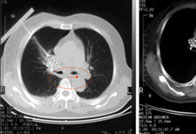

人物档案 姓名 :杨思忠 年龄 :47岁 病种 : 肺癌 人生感悟 :患有不死癌症,我很不幸。好在我从未有过悲观,做人不管什么时候,发生什么事情,都不能失去希望。 来自湖南47岁的 [阅读全文]